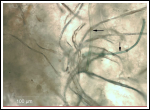

It’s characterized by a crawling/biting sensation under the skin all over your body. Lesions appear, from which tiny black, blue, red and white fibers grow. It may cause fatigue, memory loss, and problems with your vision.In short, it’s nasty… but if you claim you have it, many in...